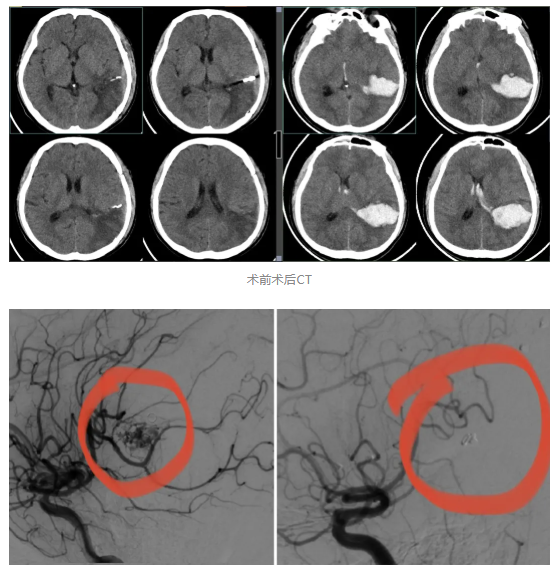

经头颅CT等系列检查,神经外科团队发现肖先生脑中藏着一枚 “隐形炸弹”—— 脑动静脉畸形,且已破裂引发大量脑出血,更危险的是,出血已导致颅内压力急剧升高,继发脑疝!“这就像颅内的‘血管迷宫’走错了路,动脉血直接冲击脆弱的静脉,破裂后形成的血肿会挤压脑组织,随时可能导致呼吸心跳骤停,死亡率极高”,神经外科邵斌主任通俗地解释道。

时间就是大脑!神经外科团队立刻启动紧急救治流程。陈国辉副主任率先为患者实施脑血管造影,精准勾勒出畸形血管团的 “全貌”—— 这是诊断脑动静脉畸形的 “金标准”,能为手术提供精准导航。

邵斌主任带领全科医生反复研讨,结合患者病情和家属意愿,最终确定 “先栓塞再切除” 的 “一站式” 复合手术方案:先通过微创介入堵住畸形血管的供血 “粮草”,再开颅完整切除病灶、清除血肿,既降低手术风险,又能最大程度保护脑功能。

3月10日,手术在DSA导管室拉开序幕。陈国辉副主任操作比头发丝还细的微导管,运用介入同轴漂浮微导管技术,精准将栓塞材料注入畸形血管团,成功阻断主要供血动脉;随后患者转至中心手术室,邵斌主任与姜昊主任默契配合,在显微镜下历经6个多小时精细操作,完整切除了畸形血管团,彻底清除颅内血肿。整个过程中,医生团队如同 “拆弹专家”,既确保 “炸弹” 完全拆除,又完好保护了周围正常的神经和血管。

术前术后DSA